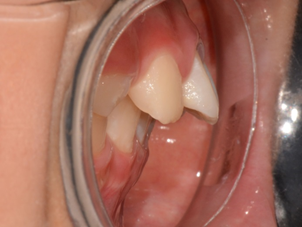

4~5세의 어린 나이임에도 불구하고 다수의 충치를 가진 소아 환자를 종종 목격할 수 있다. 특히 웬만하면 치아 우식에 이환되지 않는 상악 유전치(앞니)에도 병소가 있는 경우, 치의학계에서는 중증 유아기 우식증(SECC: Severe Early Childhood Caries)이라고 규정하는데 대부분 수유와 연관된다. 아이가 수면 도중 깨어나서 계속 울 때, 수유를 통해 울음을 그치게 하고 잠을 다시 재우는 경우가 많다. 수면 중에는 타액분비량이 적기 때문에 모유 속의 영양분이 구강 내에 저류하게 되고, 이때 SECC가 발생할 가능성이 높다. 우유도 마찬가지여서 젖병을 물거나 입 안에 액체를 머금은 상태로 잠들게 되면 SECC에 쉽게 노출된다. 며칠 전에 만 3세의 SECC 소아환자를 검진하면서 수면 중의 불가피한 수유 이후 거즈로 구강 내를 한번 닦아내는 최소한의 세척 과정이 필요하다고 보호자에게 권고했다.

KakaoTalk_20180520_091706275.png